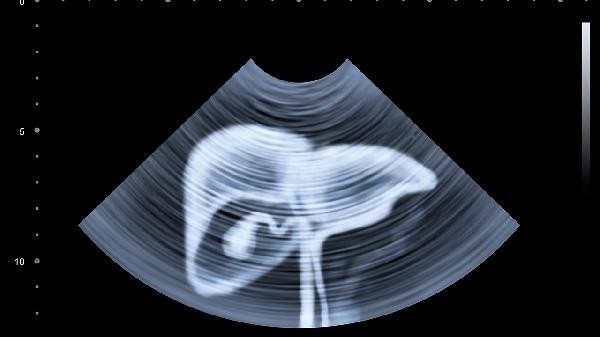

Whether liver elastography is necessary for high transaminase levels depends on the specific condition. In most cases, it is recommended to complete the examination, and in rare cases, it may not be necessary to perform it immediately. When the transaminase is mildly elevated and there are no other abnormal indicators, common causes such as viral hepatitis and fatty liver are usually given priority consideration, which can be clarified through basic examinations such as liver function review and ultrasound. If the patient has a long history of drinking, hepatitis B carrier and other high-risk factors, or the transaminase continues to be abnormal for more than 3 months, liver elastography is helpful to assess the degree of liver fibrosis. This examination has important value in staging chronic liver disease and can assist in distinguishing early changes in cirrhosis. Patients with acute drug-induced liver injury or transient elevation of transaminase may not require immediate elastography. Pregnancy, severe ascites, or obesity may affect the accuracy of testing and require a comprehensive evaluation by a doctor. Some non liver related diseases such as myocarditis and muscular dystrophy can also lead to abnormal transaminase levels, and in this case, the primary disease should be examined.